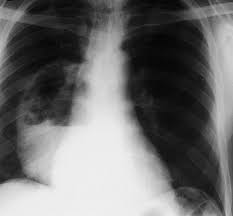

They did a cat scan and said the nod was.08 or 08 centimeters in dia. Here's why cancer can look like an infection: Pneumonia is a common lung infection. Note the increased soft tissue opacity in the lungs that partially obscures blood vessel margins. Malignant tumors trigger inflammation in surrounding normal lung tissue, and they may obstruct. Your veterinarian may recommend an fna and cytology or a biopsy, to confirm the diagnosis, and determine exactly what kind of lung cancer is present. Lung cancer develops due to the overgrowth of. You can see on the left of the image a dark (relatively clear) lung.

Dog pneumonia or lung cancer. Lung cancer develops due to the overgrowth of. Everybody still looks at lung cancer as a smoker's disease, but i never smoked. They won't say i have lung cancer but they need to do this pet sacn to rule it out. Lung cancer is actually the number one killer when it comes to cancers. You can see on the left of the image a dark (relatively clear) lung. They did a cat scan and said the nod was.08 or 08 centimeters in dia. Primary lung cancer are frequently located in the caudal (towards the hind end of the pet) lung lobes, however can be located in any lung lobe and are usually a single mass in the lungs, unless the tumor has spread. Pneumonia in people with lung cancer. Lung cancer can predispose one to pneumonia but in that case the pneumonia would recur in the same place in your lung each time. This is not to say the effects on a loved dog's body are the same as an infection. Note the increased soft tissue opacity in the lungs that partially obscures blood vessel margins. A definitive diagnosis of lung cancer requires a sample of tissue (biopsy).